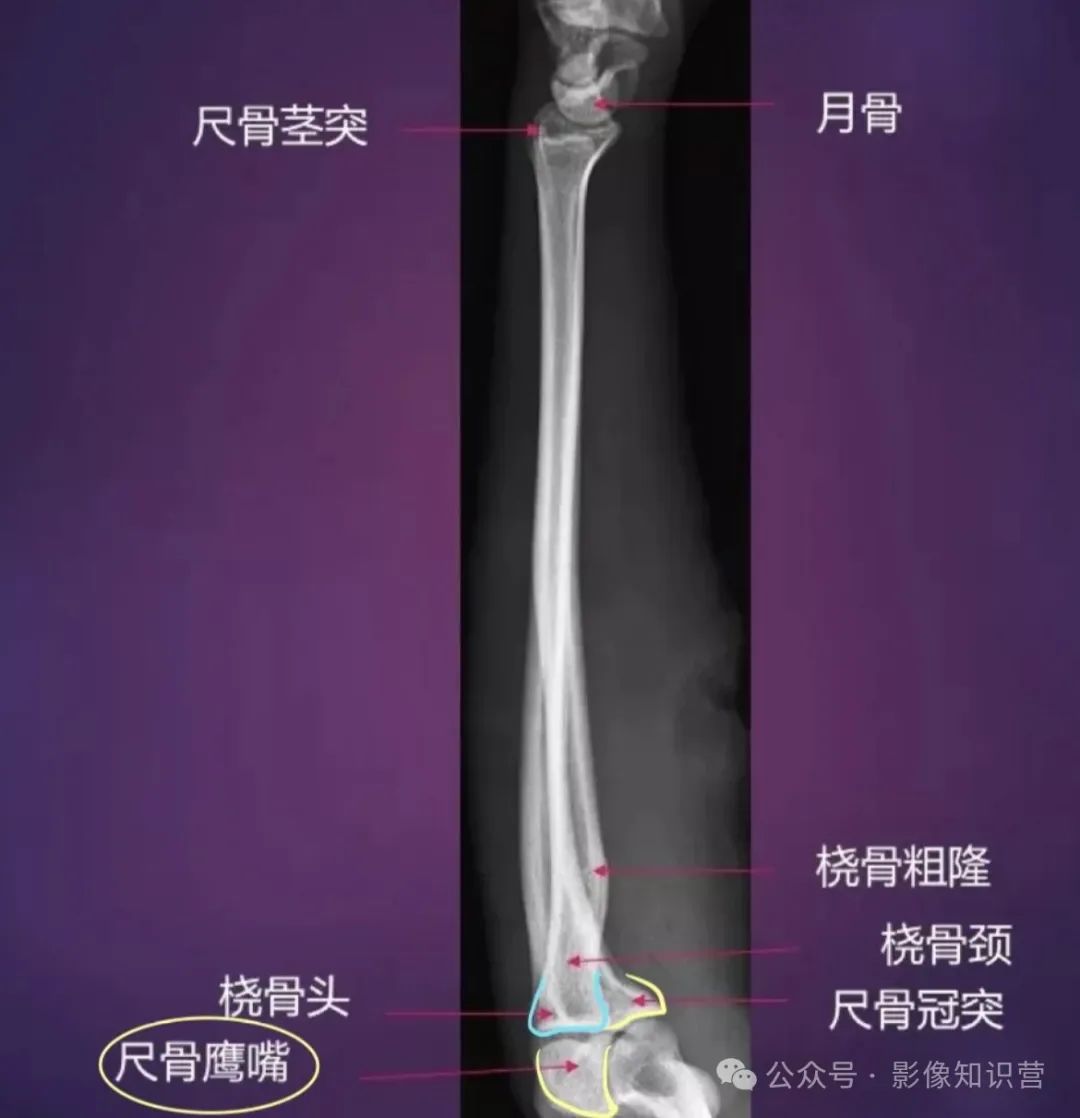

前臂

骨骼组成:桡骨(近端为桡骨头,远端为桡骨茎突)和尺骨(鹰嘴、尺骨茎突)。

影像要点:观察桡骨和尺骨的解剖对位,如桡骨茎突较尺骨茎突低约1cm。

桡骨:位于前臂外侧。上端为桡骨头,头上面的关节凹与肱骨小头相关节。桡骨下端外侧有茎突,内侧面有尺切迹与尺骨头相关节。

尺骨:位于前臂内侧。冠突前有尺骨粗隆,冠突外有桡切迹与桡骨头相关节。尺骨下端为尺骨头,其内侧有尺骨茎突。